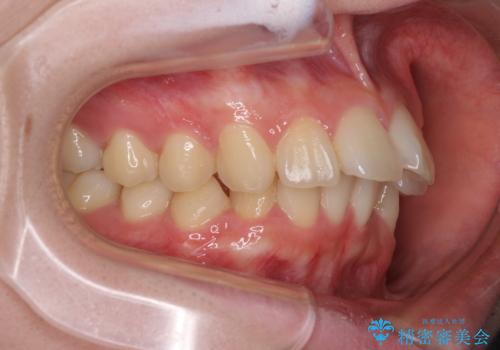

口元の突出感はないものの、上顎前歯が前方に傾斜して突出しており、前後に大きなズレがあり非常に深い咬み合わせとなっていました。

前突間を改善するため、上顎左右の第一小臼歯を抜歯してワイヤー装置にて矯正治療を行うこととしました。